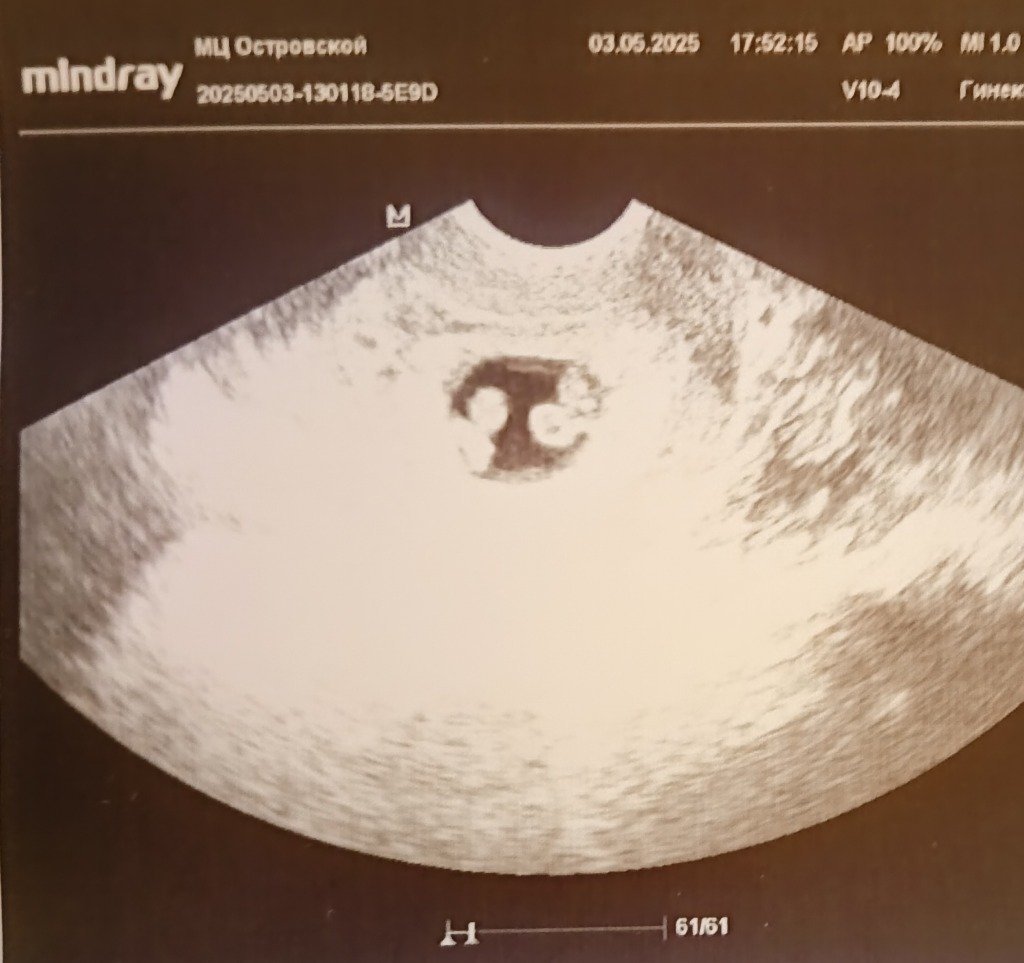

А тут мы видим двоих и два сердечка дружно стучат!)) Мама плачет, моё сердце стучит быстрее, чем у этих двоих)) Пойдём, говорю, папу озадачим)) Фото показываю: " Что Вы видите?" А он глазами хлопает, эмоции сдерживает))

Выражаем большую благодарность Клинике МАМА и особенно врачу Лучину Ивану Андреевичу.

P.S. Эта фотография — лучший подарок!!!